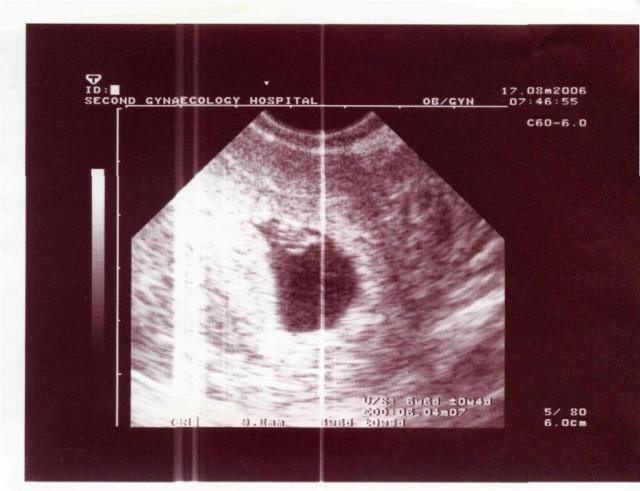

Това снимка от вагинален ехограф ли е ?? В 8 седмица с вагинален се вижда това :

Troy шЪ мЪ прощаваш,ама това фото е в 9 г.с почти Wink

не почти, а съвсем Simple Smile

това е каквото намерих в интернет - 6г.с. и 6дни

Аз намерих моите от самото начало,ако имам време ще ги скан и кача,но като гледам моята от 5г.с е подобна на снимката на момичето-вижда се някаква точка само,вече в 6 г.с и 1 ден е

по-различно.

И моята от 5 г.с. си е с една черна малка точица.

При 6 г.с. и 1 ден вече може да се види и пулс.

Да,точно тогава съм записала,че има пулс,че го и чух не само видях Simple Smile